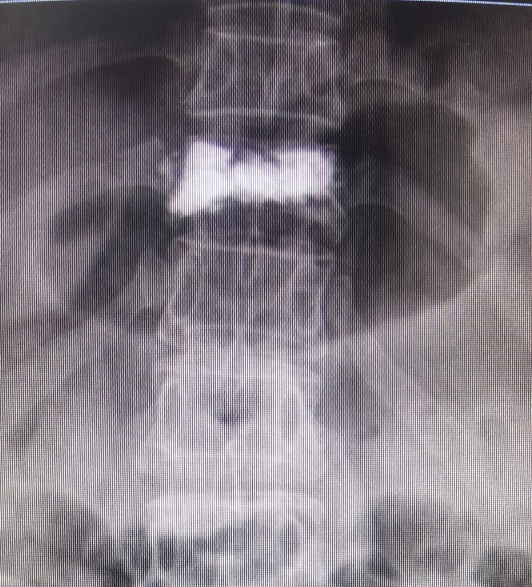

近日,交通医院外一科接待了一位特殊的腰痛病人,百岁老人宋奶奶。宋奶奶平素身体硬朗,有天散步回家跟家人说腰背痛,弯腰及起床时显著,自行口服镇痛药物疼痛缓解不明显。经外一科医师诊断,宋奶奶患上了椎体压缩性骨折。

全面评估了宋奶奶的身体状况和各项指征后,外一科医师决定为老人施行椎体压缩性骨折微创手术。该手术在局部麻醉下完成,通过微创手术稳定骨折、恢复椎体力学强度、防止椎体进一步压缩和缓解疼痛。并且有手术切口小,无需缝合,对身体状况要求低,术后恢复快等优势。对于平常慢性病较多,体质较弱的老年人尤其适用。